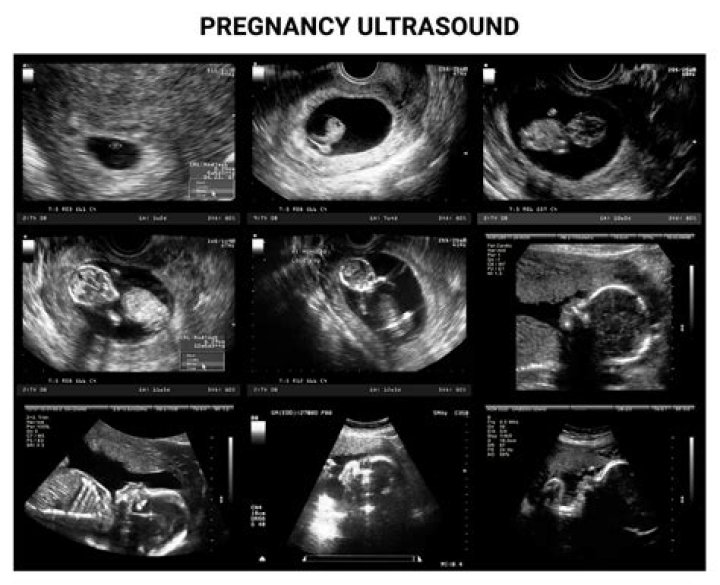

Pregnancy ultrasounds

Why is ultrasound done in pregnancy?

Ultrasound (also called sonogram) is a prenatal test offered to most pregnant women. It uses sound waves to show a picture of your baby in the uterus (womb). Ultrasound helps your health care provider check on your baby's health and development.

What types of ultrasounds are there for pregnancy?

According to the American Pregnancy Association, there are seven different types.

• Transvaginal Scans. ...

• Standard Baby Ultrasounds. ...

• Advanced Baby Ultrasounds. ...

• Doppler Ultrasounds. ...

• 3D Baby Ultrasounds. ...

• 4D Baby Ultrasounds. ...

• Fetal Echocardiography.

When is the best time to scan during pregnancy?

Most practitioners wait until at least 6 weeks to perform the first pregnancy ultrasound. However, a gestational sac can be seen as early as 4 1/2 weeks after your last period, and a fetal heartbeat can be detected at 5 to 6 weeks (though that isn't always the case).

Your First Ultrasound

It's typically done between 7 and 8 weeks to verify your due date, to look for a fetal heartbeat, and to measure the length of the baby from “crown to rump.” At this ultrasound, you'll also learn whether you're having one baby, twins, or more!